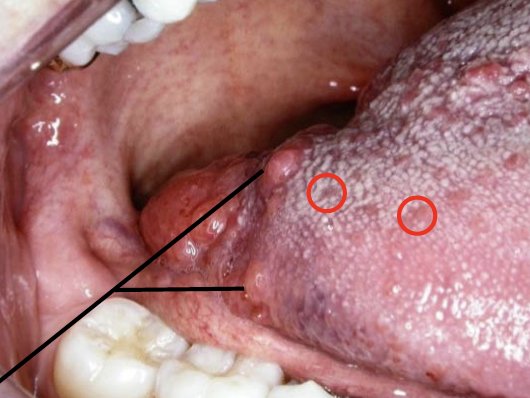

舌頭

Structure

- Terminal sulcus(terminalis)分前後

Oropharynx

Sensor:CN IX

由外而內

- Palatoglossal fold(arch)

- Palatine tonsil

- Palatopharyngeal fold(arch)

- 分隔口腔與口咽(fauces)